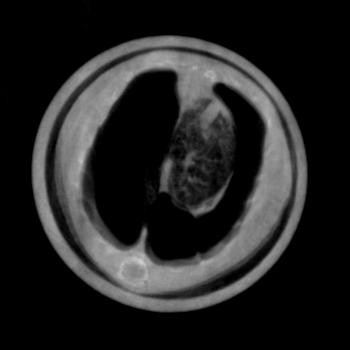

To evaluate the location of the lung tissue in the two mice computed tomographies (CT) of them were performed. This was done by rotating the object and acquiring 601 angular projections equally spaced over a full circle with the setup described in Section II.3. A reference image was taken after every 15th projection. This leads to a total of to acquire all projection images. For image reconstruction, a filtered backprojection (FBP) was applied using a ramp kernel for the absorption and the dark field data and a Hilbert kernel for the phase data after performing the phase retrieval described in Section II.2.

Exemplary for the data, one set of axial cross-sections of the lung region of the second mouse are displayed in Figure 5 (marked as horizontal lines in Figure 4). In all three CT cross-sections, the lung tissue can clearly be located in the chest of the mouse. The location found with the CT reconstruction corresponds with the location visible in the dark field projection image and the speckled area in the differential-phase image. In contrast, the exact position of the lung cannot be located with the absorption image alone.

To quantify the location of lung tissue within the mouse, a CT scan of the second mouse was performed. Its results, shown in Figure 5, substantiate the above results that lung tissue is, indeed, only present in the right part of the mouse’s chest cavity in this cross-section plane. It is imaginable that an assured diagnosis can be made without a computed tomography scan, which could lead to a quickened diagnosis and a dose saving.